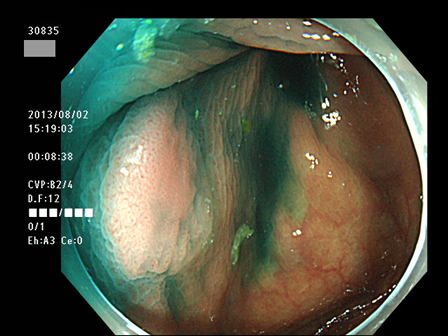

上記100名より抽出した平坦・陥凹型腺腫(=癌化の危険が高いが見落としやすい病変)の内視鏡写真

30801 30804 30805 30814 30819 30822 30823 30825 30827 30828 30829 30830 30833 30834 30835 30837 30838 30839 30840 30841 30843 30846 30848 30850 30853 30854 30855 30857 30858 30860 30862 30863 30867 30868 30870 30872 30873 30874 30875 30876 30882 30884 30886 30887 30891 30892 30893 30894 30895 30897 30898・・・・・・の52名